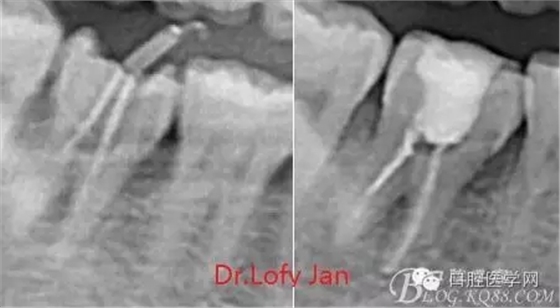

X線技術(shù)在根管治療中的重要性主要體現(xiàn)在以下幾個(gè)方面:

①有助于發(fā)現(xiàn)牙體和根尖周組織的異常改變,如牙折、牙內(nèi)吸收、髓腔鈣化及根尖囊腫;

②有助于確定牙根和根管的數(shù)目、位置、形態(tài)、方向和彎曲情況;

③有助于了解以前曾作過的治療情況,為再治療提供依據(jù);

④在操作前估計(jì)根管的工作長(zhǎng)度;

⑤評(píng)價(jià)根管充填的質(zhì)量以及療效。